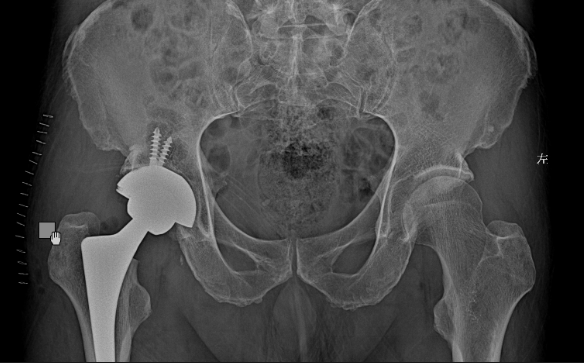

65岁的孙大伯,走路时不慎滑倒摔伤,值班医生马上为大伯做了检查,发现右股骨颈骨折;还有81岁的李爷爷,作为体育爱好者,在骑自行车锻炼的时候一不当心摔伤,检查结果也是右股骨颈骨折。两人就相隔一天,都相继入住康华医院骨2科。

李某 ——男——81岁

经过术前检查评估,两位老人都做了人工全髋关节置换术。手术过程顺利,第2天就已经可以下地活动行走。病人和家属的脸上也一扫前几天的阴霾,露出了开心的笑容。